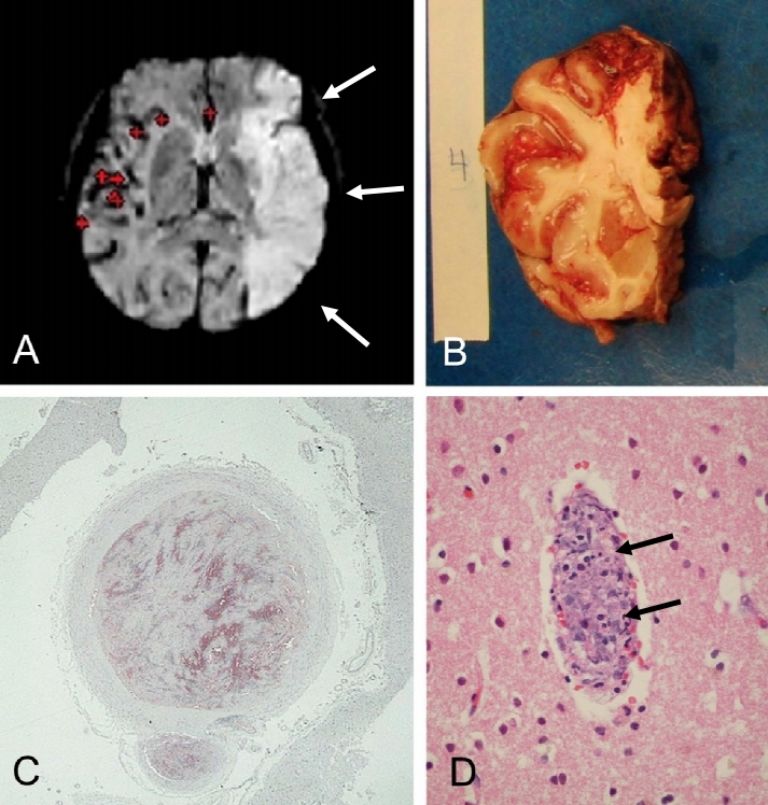

El estudio detalló que la mayoría de los síntomas neurológicos asociados al Covid-19 se pueden deber a reacciones sistémicas, como sepsis, mecanismos autoinmunes o insuficiencia multiorgánica.

Además, señala que el coronavirus puede ocasionar una neuropatología aguda, dejando algunas huellas en el cerebro, como encefalitis e infartos agudos.

El virus también puede 'esconderse' en el cerebro, lo que provocaría que existan reinfecciones, ya que, aunque no haya rastros de él en los pulmones, todavía estaría dentro del organismo del afectado.